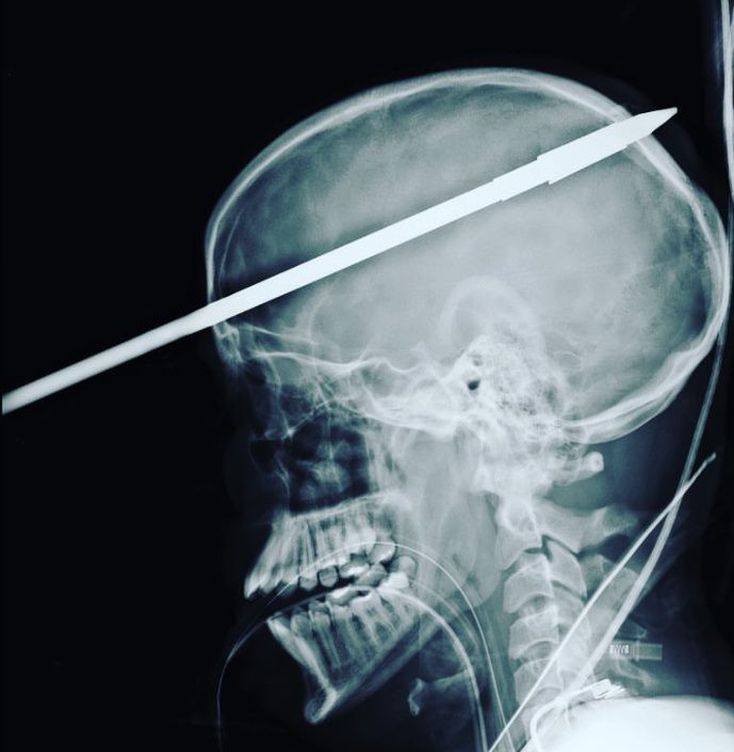

16 year old boy survived after being implanted in the head by a fishing spear.The x ray image showed that the spear had went all the way through Lopez's head at the angle that just missed his eyes and dodged all the major blood vessels in his brain.Doctor said that it had propelled through the right hemisphere of the boy's brain,juat less than 1 inch above the central brain that control the senses,heart rate and breathing.Fire rescued tool is used to cut the spear so that proper x ray should be taken.Rest of the spear is removed in 3 hour surgery.The boy doesn't remember the accident.